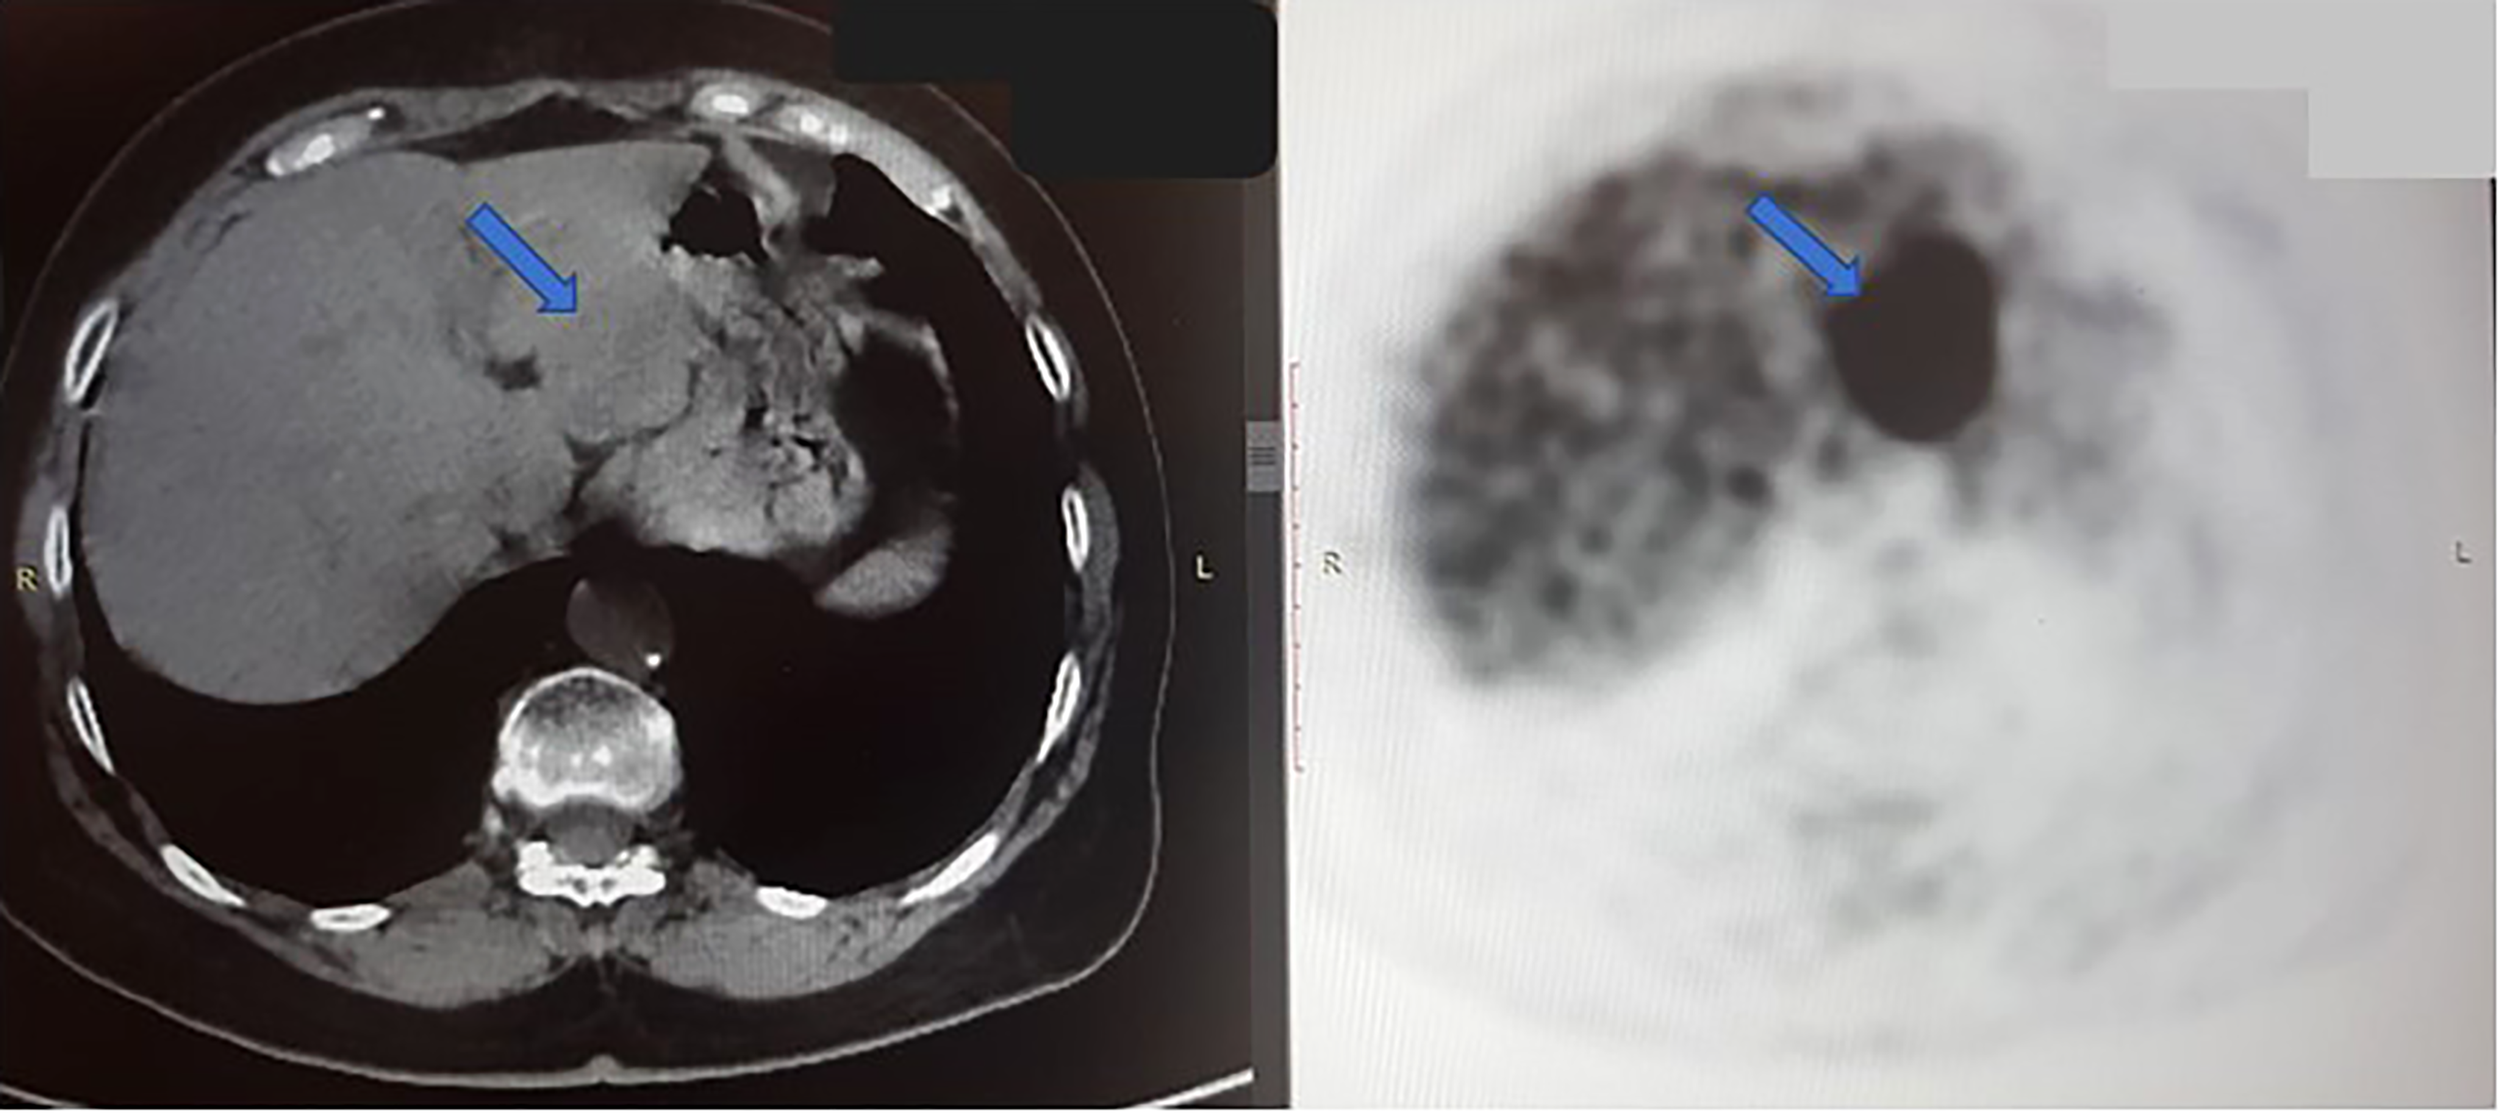

Disease progression was identified in January 2019 with a further enlargement of the single liver mass. Tests for T790M-mut were negative. The patient was then enrolled in a clinical trial where she received combined chemo-immunotherapy with platinum-based therapy and pembrolizumab. In November 2019, there was a size progression of the liver mass, prompting a liquid biopsy evaluation that identified progression of both L858R (8.2%) and L833V (7.2%) EGFR mutations, as illustrated in Table 1. The patient was then treated with liver stereotactic body radiation therapy (SBRT) of 50 Gy in 5 fractions. She continued maintenance therapy with oral vinorelbine until October 2020. Due to the continued liver mass progression, the patient underwent a left hepatectomy (Figure 2). Biopsy of the liver mass showed moderate to poorly differentiated adenocarcinoma, of lung origin, with Met-amplification (Table 1).

Figure 2

Axial CT scan (left) and PET scan (right) from October 2020, shows a large tumor in the left hepatic lobe (blue arrow). In PET scan, the dark mass shows an FDG-avid, metabolically active tumor. The right hepatic lobe is normal, without signs of malignancy at this time.

In December 2020, multiple liver metastases were identified on PET-CT (Figure 3A). At this time, another comprehensive genomic test (Tempus) was performed which identified further progression of EGFR- L858R (61.1%) and L833V mutations (63.4%), as well as the development of additional findings such as CEP85L-ROS1 fusion and MET amplification (6 copies), as shown in Table 1. Treatment with osimertinib (80mg daily) was then attempted, but the disease continued progressing (Figure 3B). At this time, crizotinib (250 mg bid) was added to the current regimen. Following 2-months of combination therapy, the liver mass substantially decreased in its size and numbers (Figure 3C). Dose reduction of crizotinib (250 mg once daily) was required following an ischemic stroke. In October 2021, the patient passed away due to further disease progression.

Figure 3

(A) Coronal section, superimposed PET-CT scan, December 2020. Four years after the first presentation of stage 3B NSCLC, the right lung shows a significant reduction in FDG-18 uptake and decreased tumor size, with only a scar, indicating the lung’s complete response to treatment. However, status-post left hepatectomy, there is increased FDG-18 uptake in the right lobe of the liver, consistent with multifocal right hepatic metastatic disease. (B) Two months later, February 2021, there is further progression in size, number, and metabolic activity of metastases throughout the right lobe of the liver, indicating more aggressive disease. There remains no evidence of recurrent or residual disease in the lung. (C) Non-contrast, axial CT scan from April 2021 shows interval regression in size and number of liver masses. The white spots are sutures from the surgery to remove the left hepatic lobe (status-post left hepatectomy).